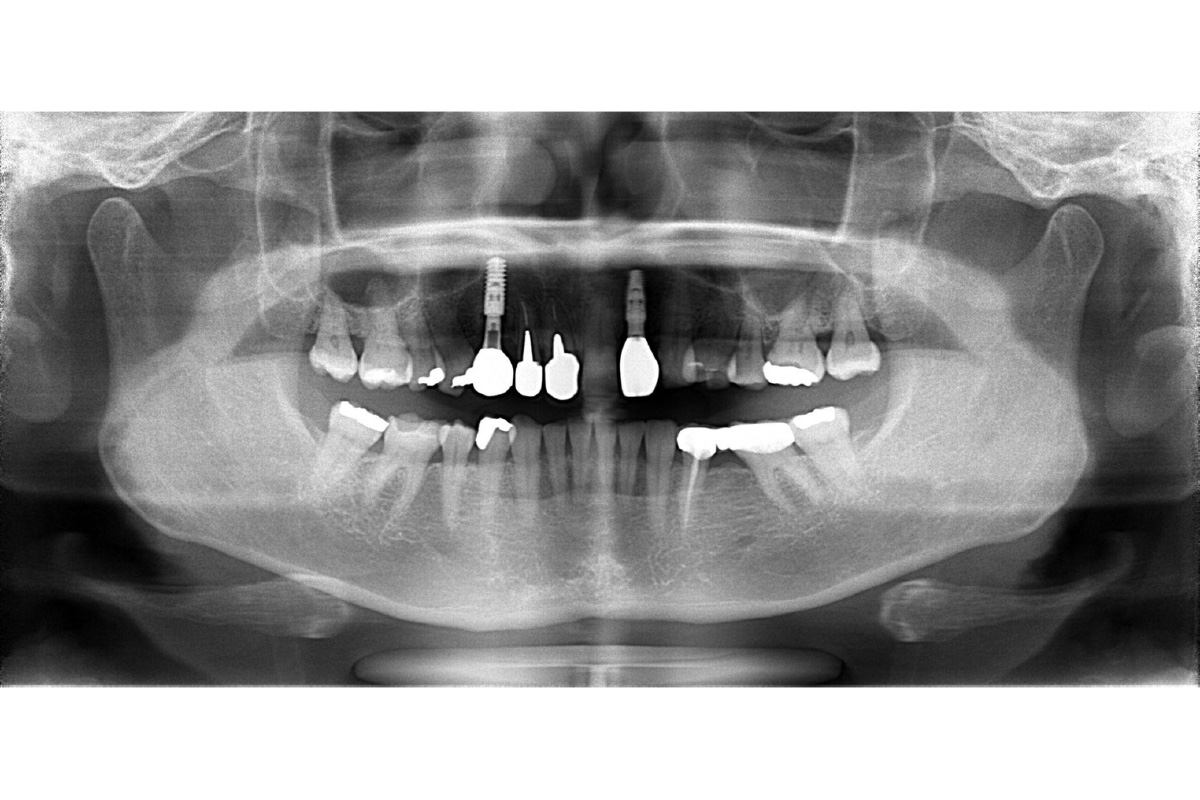

治療後

| 主訴 | 左上の前歯が折れた。 インプラントで治したい。 |

| 期間 | 4ヵ月 |

| 費用 | 628,650円(治療時) |

| 治療内容 | インプラント治療(抜歯即時埋入) 骨造成 結合組織移植術 |